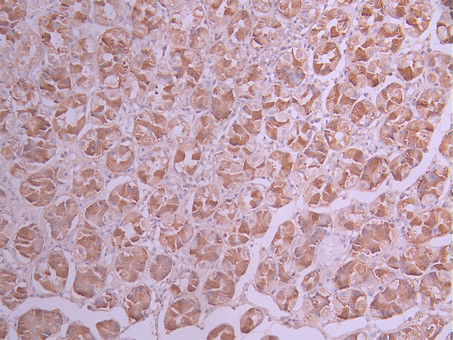

IHC image of CSB-RA969203A0HU diluted at 1:100 and staining in paraffin-embedded human colorectal cancer performed on a Leica BondTM system. After dewaxing and hydration, antigen retrieval was mediated by high pressure in a citrate buffer (pH 6.0). Section was blocked with 10% normal goat serum 30min at RT. Then primary antibody (1% BSA) was incubated at 4°C overnight. The primary is detected by a Goat anti-rabbit polymer IgG labeled by HRP and visualized using 0.05% DAB.

IHC image of CSB-RA969203A0HU diluted at 1:100 and staining in paraffin-embedded human stomach tissue performed on a Leica BondTM system. After dewaxing and hydration, antigen retrieval was mediated by high pressure in a citrate buffer (pH 6.0). Section was blocked with 10% normal goat serum 30min at RT. Then primary antibody (1% BSA) was incubated at 4°C overnight. The primary is detected by a Goat anti-rabbit polymer IgG labeled by HRP and visualized using 0.05% DAB.